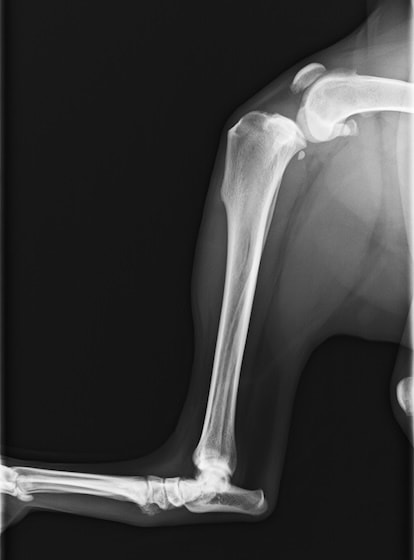

前十字靱帯断裂症例(2025/02/06)

HPの外科の前十字靱帯断裂のページに、犬のTPLO(脛骨高平部水平化骨切り術)手術を行った症例を追加致しました。大腿骨と脛骨を繋ぐ靱帯の一つである前十字靱帯が断裂すると、膝の関節が不安定となり関節炎が進行します。また膝関節内のクッションの役割を果たしている半月板にもダメージが加わり、痛みを生じて正常な歩行が出来なくなります。治療法としては術後の機能回復の早さから、近年ではTPLO法(脛骨の一部を円形に切り、角度を調整し膝関節を安定化させる手術)が多く選択されています。前十字靭帯断裂は中高齢犬によく見られる病気であり、膝蓋骨脱臼に併発することもあります。気になる症状がある場合はお早めにご相談下さい。